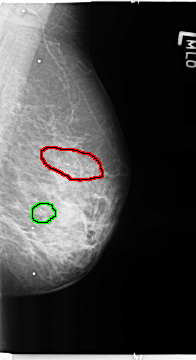

FILE: B_3364_1.LEFT_MLO.OVERLAY

TOTAL_ABNORMALITIES 2

ABNORMALITY 1

LESION_TYPE CALCIFICATION TYPE PLEOMORPHIC DISTRIBUTION CLUSTERED-SEGMENTAL

ASSESSMENT 4

SUBTLETY 4

PATHOLOGY BENIGN

TOTAL_OUTLINES 1

BOUNDARY

ABNORMALITY 2